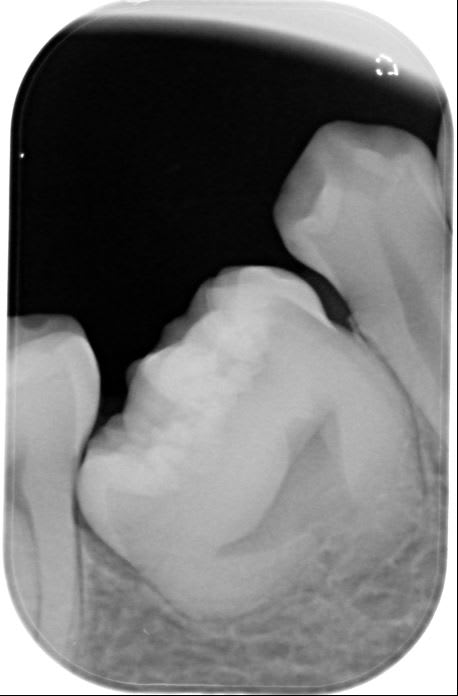

Tiens regarde une dent en forme de coeur....

Joli coeur effectivement, merci la miss mais sinon c'est pas non plus trop sympa pour le patient cette dent, non? T'as prevu quoi?

Et pour répondre à algi sur la dent en forme de coeur, bah, elle a rien alors je lui fais rien. Juste prévenu le patient sur le brossage inter proximal ;-))